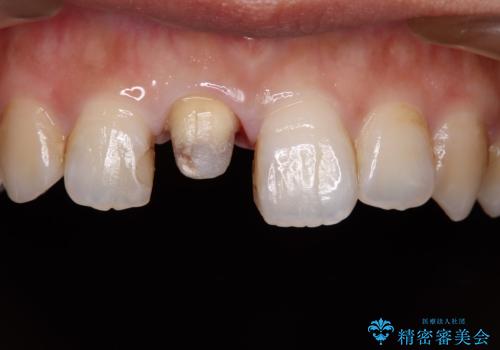

不適合な被せものを除去し、土台の歯の形を修正し、精度の高いシリコーンによる型どりをしました。